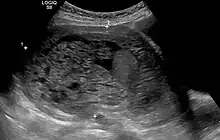

Molar pregnancy in ultrasound -